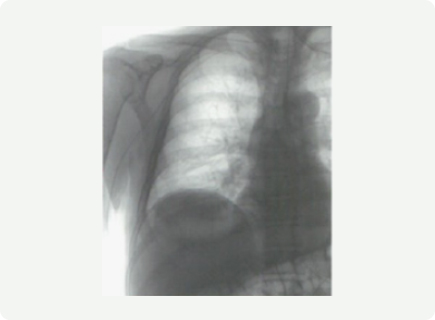

우측 전완의 척측피정맥을 통해서 중심정맥도관이 삽입된 모습

PICC 삽입 후 가슴 X-ray 촬영을 통해 정확하게 위치하는지를 확인